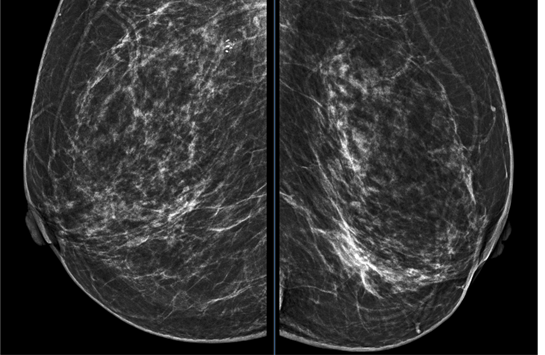

X-quang tuyến vú 2 bên. Hình ảnh đám tăng đậm độ bất xứng ¼ dưới trong bên trái

Tại Bệnh viện Bạch Mai, bệnh nhân được chụp X-quang tuyến vú hai bên, phát hiện vùng tăng đậm độ bất xứng ở 1/4 dưới trong vú trái, xếp loại BIRADS 4. Siêu âm tuyến vú ghi nhận tại vị trí 9 giờ vú trái, cách núm vú 1cm có nhân giảm âm, kích thước 6x3mm (BIRADS 3). Kết quả chọc hút tế bào cho thấy hình ảnh ung thư biểu mô vú, do đó bệnh nhân được chuyển đến Trung tâm Y học hạt nhân và Ung bướu để tiếp tục đánh giá và điều trị.